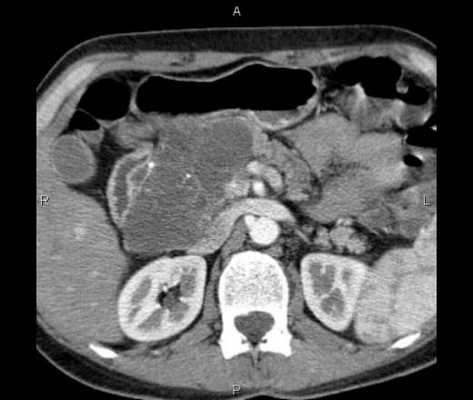

(Слева) При аксиальной КТ с контрастом у молодою человека, находящегося на ИВЛ после аварии на мотоцикле, выявлен напряженный пневмоторакс с правой стороны и малый пневмоторакс слева. Газ под давлением распространяется вдоль около-диафрагмальной жировой клетчатки.

(Справа) На аксиальном КТ срезе у этого же пациента визуализируется внепросветный воздух из грудной полости, распространяющийся в брюшную полость, очерчивающий контуры петель кишечника. Нет повреждения органов брюшной полости. (Слева) На аксиальном КТ срезе (с контрастным усилением) у пожилого пациента, находящегося на вентиляции легких под давлением, с документированным двухсторонним пневмотораксом и пневмомедиастинумом, визуализируется газ, распространяющийся под давлением в брюшную полость, забрюшинное пространство и брыжейку.

(Справа) На аксиальном срезе (КТ с контрастом) у этого же пациента в дополнение к обширному скоплению газа в забрюшинном пространстве визуализируется газ в брюшной полости. В подобных случаях газ может распространяться в кишечной стенке, симулируя пневматоз в результате ишемии.

(Справа) На аксиальном КТ срезе у этого же пациента визуализируется внепросветный воздух из грудной полости, распространяющийся в брюшную полость, очерчивающий контуры петель кишечника. Нет повреждения органов брюшной полости.

(Слева) На аксиальном КТ срезе (с контрастным усилением) у пожилого пациента, находящегося на вентиляции легких под давлением, с документированным двухсторонним пневмотораксом и пневмомедиастинумом, визуализируется газ, распространяющийся под давлением в брюшную полость, забрюшинное пространство и брыжейку.